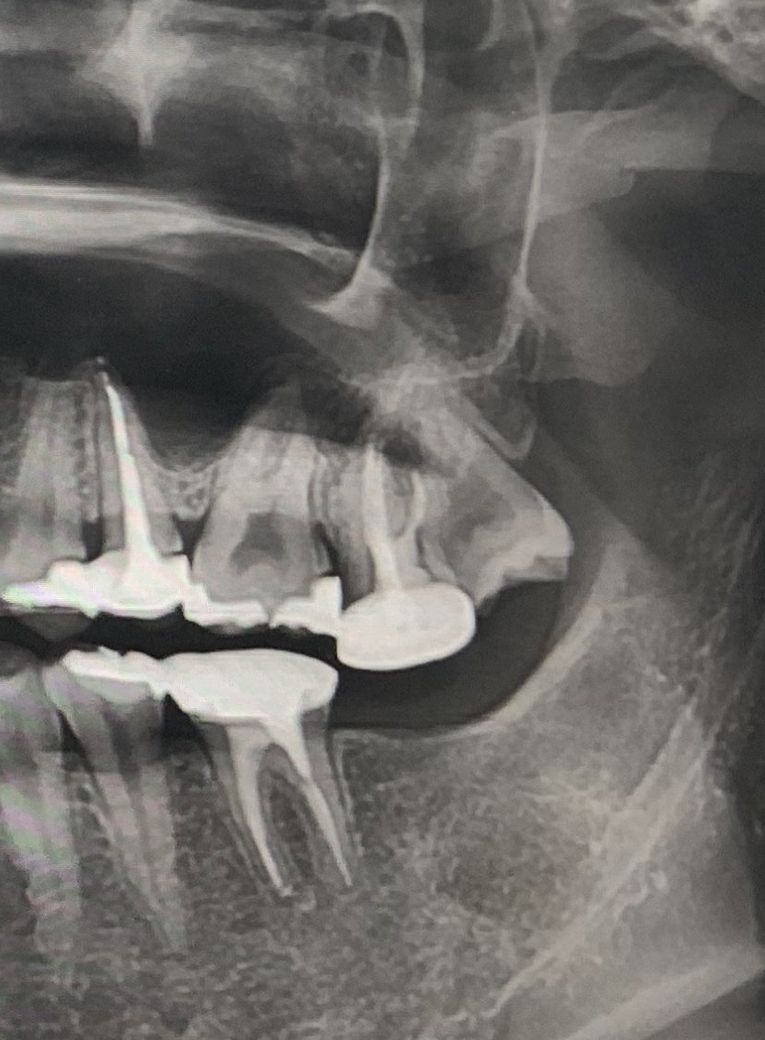

#27치아의 경우는 뿌리쪽 사진으로만 봤을경우에는 뿌리에 염증이 있는것을 정확하기 확인하기는 힘들어 보입니다.

하지만 크라운치료가 된 내부에 음영이 보이는것을 봐서 충치등에 의해서 치아 내부에 부식이 생기고 염증이 유발했을수 있음을 유추해볼수는 있어요.

현재 사진으로는 정확히 보이지는 않지만 사랑니 앞의 어금니 부위에 염증이 있어 보입니다.

해당 치아의 대합되는 치아 ( 맞물리는 치아)도 발치되어 오랜 기간 방치되어 문제가 생긴 치아 자체도 솟구쳐 올라와 보입니다.

치아 상태가 많이 안좋아 보여집니다. 대합치가 오랜기간동안 발치된상태로 방치되셔서 신경치료 하신 치아가 많이 정출되기도 하셧네요. 보철물때문에 안에 상황을 정확히 알수는 없지만 보철물을 벗겨내면 안쪽상태가 꽤 나쁠껄로 예측이 됩니다.